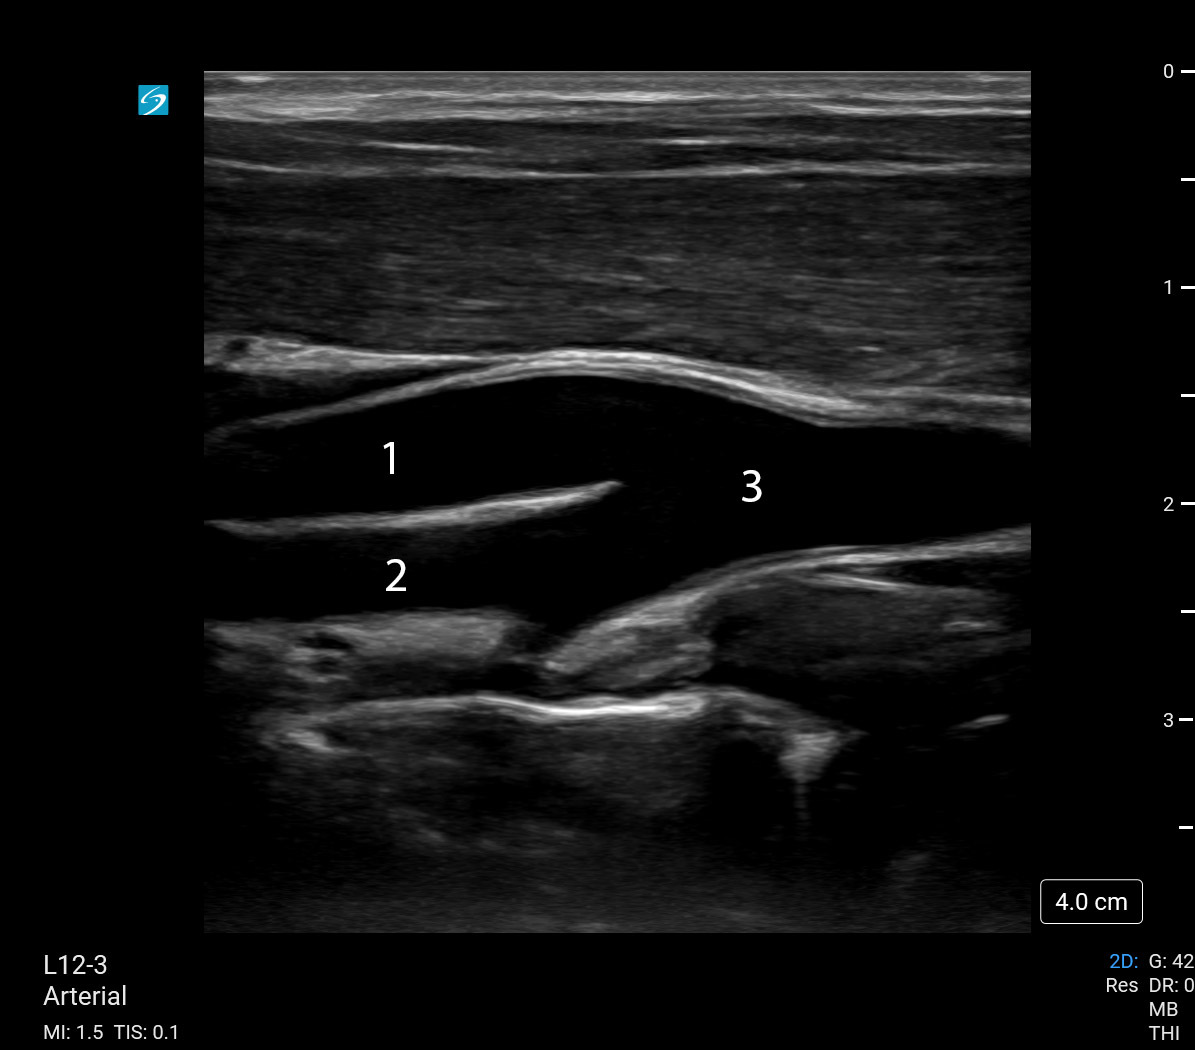

颈动脉分叉图像

颈外动脉 (ECA)

颈内动脉 (ICA)

颈总动脉 (CCA)